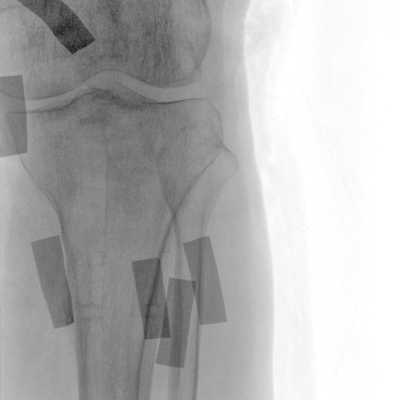

在球管和平板探測器兩端,分別加裝了激光定位系統,滿足不同擺位無射線下的定位需求,降低醫患輻射劑量的同時,提高臨床工作效率。

具備束光器預覽功能,可以在無射線狀態下,實現曝光范圍大小的調節;大幅減少臨床反復曝光帶來的射線輻射;并自動調整圖像興趣區大小與位置,使自動模式更準確。

濾線柵可插拔式設計符合行業標準,用于兒科和其他劑量敏感的臨床應用,使用簡便,保障圖像清晰的同時,可有效防護輻射危害。